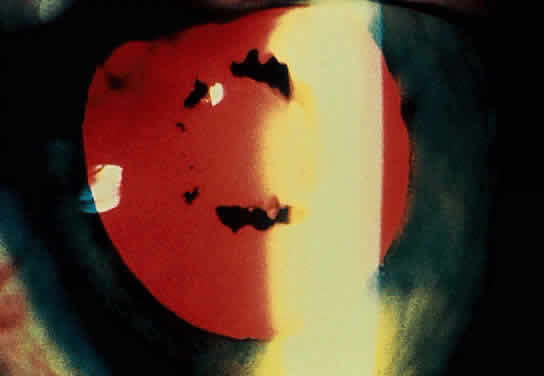

The acute iridocyclitis is suggestive of vascular occlusive changes, or acute tissue damage, with sudden onset and massive outpouring of cells into the anterior chamber or vitreous (Fig. 10). Vascular injection is not as pronounced as the number of cells in the anterior chamber or vitreous would suggest, and protein in the anterior chamber may be minimal. The cells settle to the dependent portion of the anterior chamber, forming a hypopyon. There may be little tendency toward formation of keratic precipitates. The process may be unilateral or bilateral. Episodes usually are recurrent, and recurrences produce increased tissue damage, progressing to more chronic involvement. All vascular tissues of the eye may become involved, including episcleritis, scleritis, iridocyclitis, retinal and choroidal vasculitis, and optic neuritis. Retinal focal ischemic areas of edema and optic nerve edema (Fig. 11) are seen in the acute phases, and retinal and optic nerve atrophy along with retinal pigment epithelial changes resembling secondary retinitis pigmentosa, attenuation, and sheathing of retinal vessels are seen in the later stages of ocular involvement.76,91–93

Fig. 10. Hypopyon, iris sector ischemia, posterior synechiae and cataract formation in severe iridocyclitis with Behçet's disease.

Fig. 11. Optic nerve and retinal edema with cells in the vitreous in posterior involvement with acute Behçet's disease.